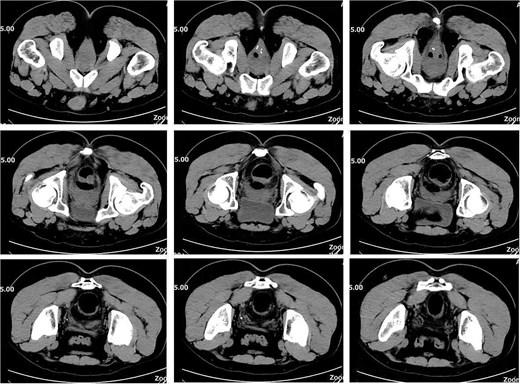

On postoperative Day 15, a complete blood count showed a white blood cell count of 9.12 × 109/l and a neutrophil percentage of 77.5%. Pelvic CT demonstrated rectal wall edema, anterior wall perforation, and partial absorption of the surrounding infection, indicating reduced infection severity compared to the previous scan on postoperative Day 10 (Fig. 3). Given the patient’s satisfactory response to antibiotic therapy and absence of ongoing infection signs, intravenous antibiotic treatment was discontinued.